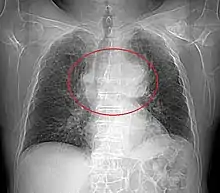

Radiographie thoracique

La radiographie thoracique permet de visualiser entre 45 % et 80 % des tumeurs thymiques[29]. De face, elles présentent un aspect bien délimité, parfois lobulé, débordant d'un côté du médiastin. Le profil permet d'affirmer le caractère rétrosternal de la tumeur, et donc sa localisation dans le médiastin antérieur. Les signes d'envahissement sont rares et peu visibles, et comprennent principalement l'ascension d'une coupole diaphragmatique, faisant suspecter un envahissement du nerf phrénique[28].

Présentation tomodensitométrique classique d'un thymome à un stade précoce (cercle rouge). À l'arrière, l'aorte, la veine cave supérieure et l'artère pulmonaire sont visibles en coupe.